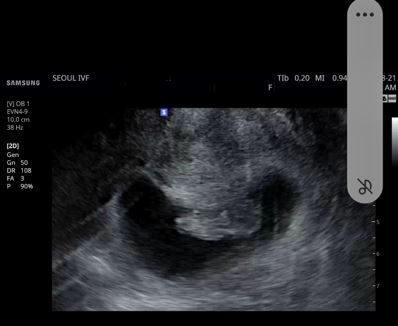

| 가슴 떨리는 임신 이야기를 공유해 주세요. | 저는 결혼이 늦었어요. 건강검진해주신 의사분께서 6개월정도 자연임신하다 안되면 바로 난임병원 알아보라고 하셨어요. 시간을 보내다보니 쉽게 아기가 오지 않아 바로 난임병원을 알아봤어요. 친구가 알아봐준 곳과 제가 알아본 곳이 같았는데, 그 곳이 바로 서울 ivf 였어요~ 이유정원장님을 만나서 너무 감사하게도 1차만에 아이가 찾아왔습니다^^ |

| 치료 도중 느꼈던 가장 기뻤던 순간과 절망적인 것들은 무엇인가요? 잊지 못할 경험이 있나요? | 난자 채취후 이식하려고 준비하는데 살짝 피가 흐르는 것을 원장님이 캐치하셨어요. 게다가 자궁에 1cm정도 작은 혹도 있는 걸 발견해서 자궁경으로 제거하고 한달 뒤에 이식을 했어요. 그 미뤄진 한달이 참 더디게만 느껴져서 ㅜㅜ.. 그 때가 힘들었습니다. |